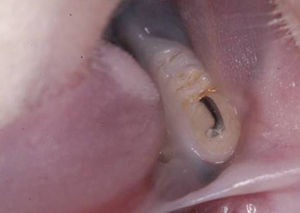

Oclusal trauma inductionIn the baseline, the animals were anesthetized by an intramuscular administration of ketamine (50–100mg/kg) (Dopalen®; Vetbrands LTDA, Jacareí, SP, Brazil) and Xylazine (10mg/kg). Their jaws were opened using the Doku apparatus (1966) to insert an orthodontic wire segment (0.5mm of diameter and approximately 1mm long) on the occlusal surface of the mandibular first molar, which was randomly chosen, to create an occlusal interference, using light-curing resin increments for the its fixation (Z100®; 3M, Sumaré, SP, Brazil).

The occlusal surface of the selected molar was previously cleaned with the aid of a microbrush, followed by the conditioning of the occlusal surface with phosphoric acid 37% (Villevie® Dentalville do Brazil, Joinville, SC, Brasil), rinsing and application of the adhesive (Single Bond®; 3M, Sumaré, SP, Brazil) according to the manufacturer specifications. The orthodontic wire's diameter standardized the height of the occlusal interference; the resin was inserted until the limit of the wire height, without exceeding it. The period of the primary occlusal trauma induction was 14 days (Fig. 1).